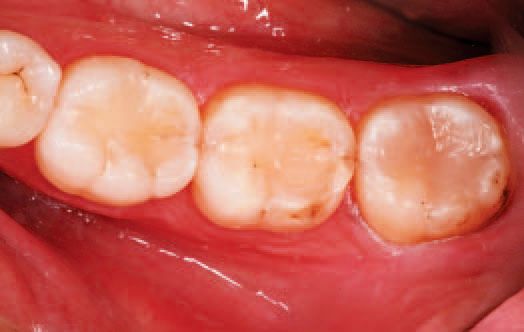

The occlusion was determined to be satisfactory and the restorations complete (Fig. 30). The patient returned the following week for a visit and reported no post-op sensitivity. After re-hydration, the excellent color-matching to the patient’s natural dentition was visible, and all three restorations appeared esthetically similar.